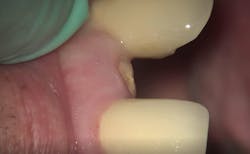

First visit: Extraction and immediate implant placement, immediate placement of the final abutment prepared intraorally, and then a provisional out of function.

Second visit: After two months of healing, final impressions were taken.

Third visit: The final crown was delivered.

The implant was allowed to heal for two months before impressions were taken. The final zirconia crown was delivered two weeks later (figure 6).